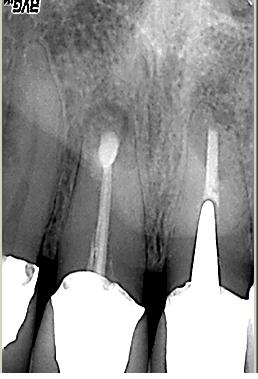

Abschlusskontrolle der WF

Abschlusskontrolle der WF im Oktober 2002. Man beachte die dreidimensionale Füllung des apikalen Deltas des distalen Kanalsystems (hier konnte Patency etabliert werden) sowie die Füllung der Seitenkanäle im Bereich der Furkation, auf deren Höhe sich auch der lingualen Abszeß befand.